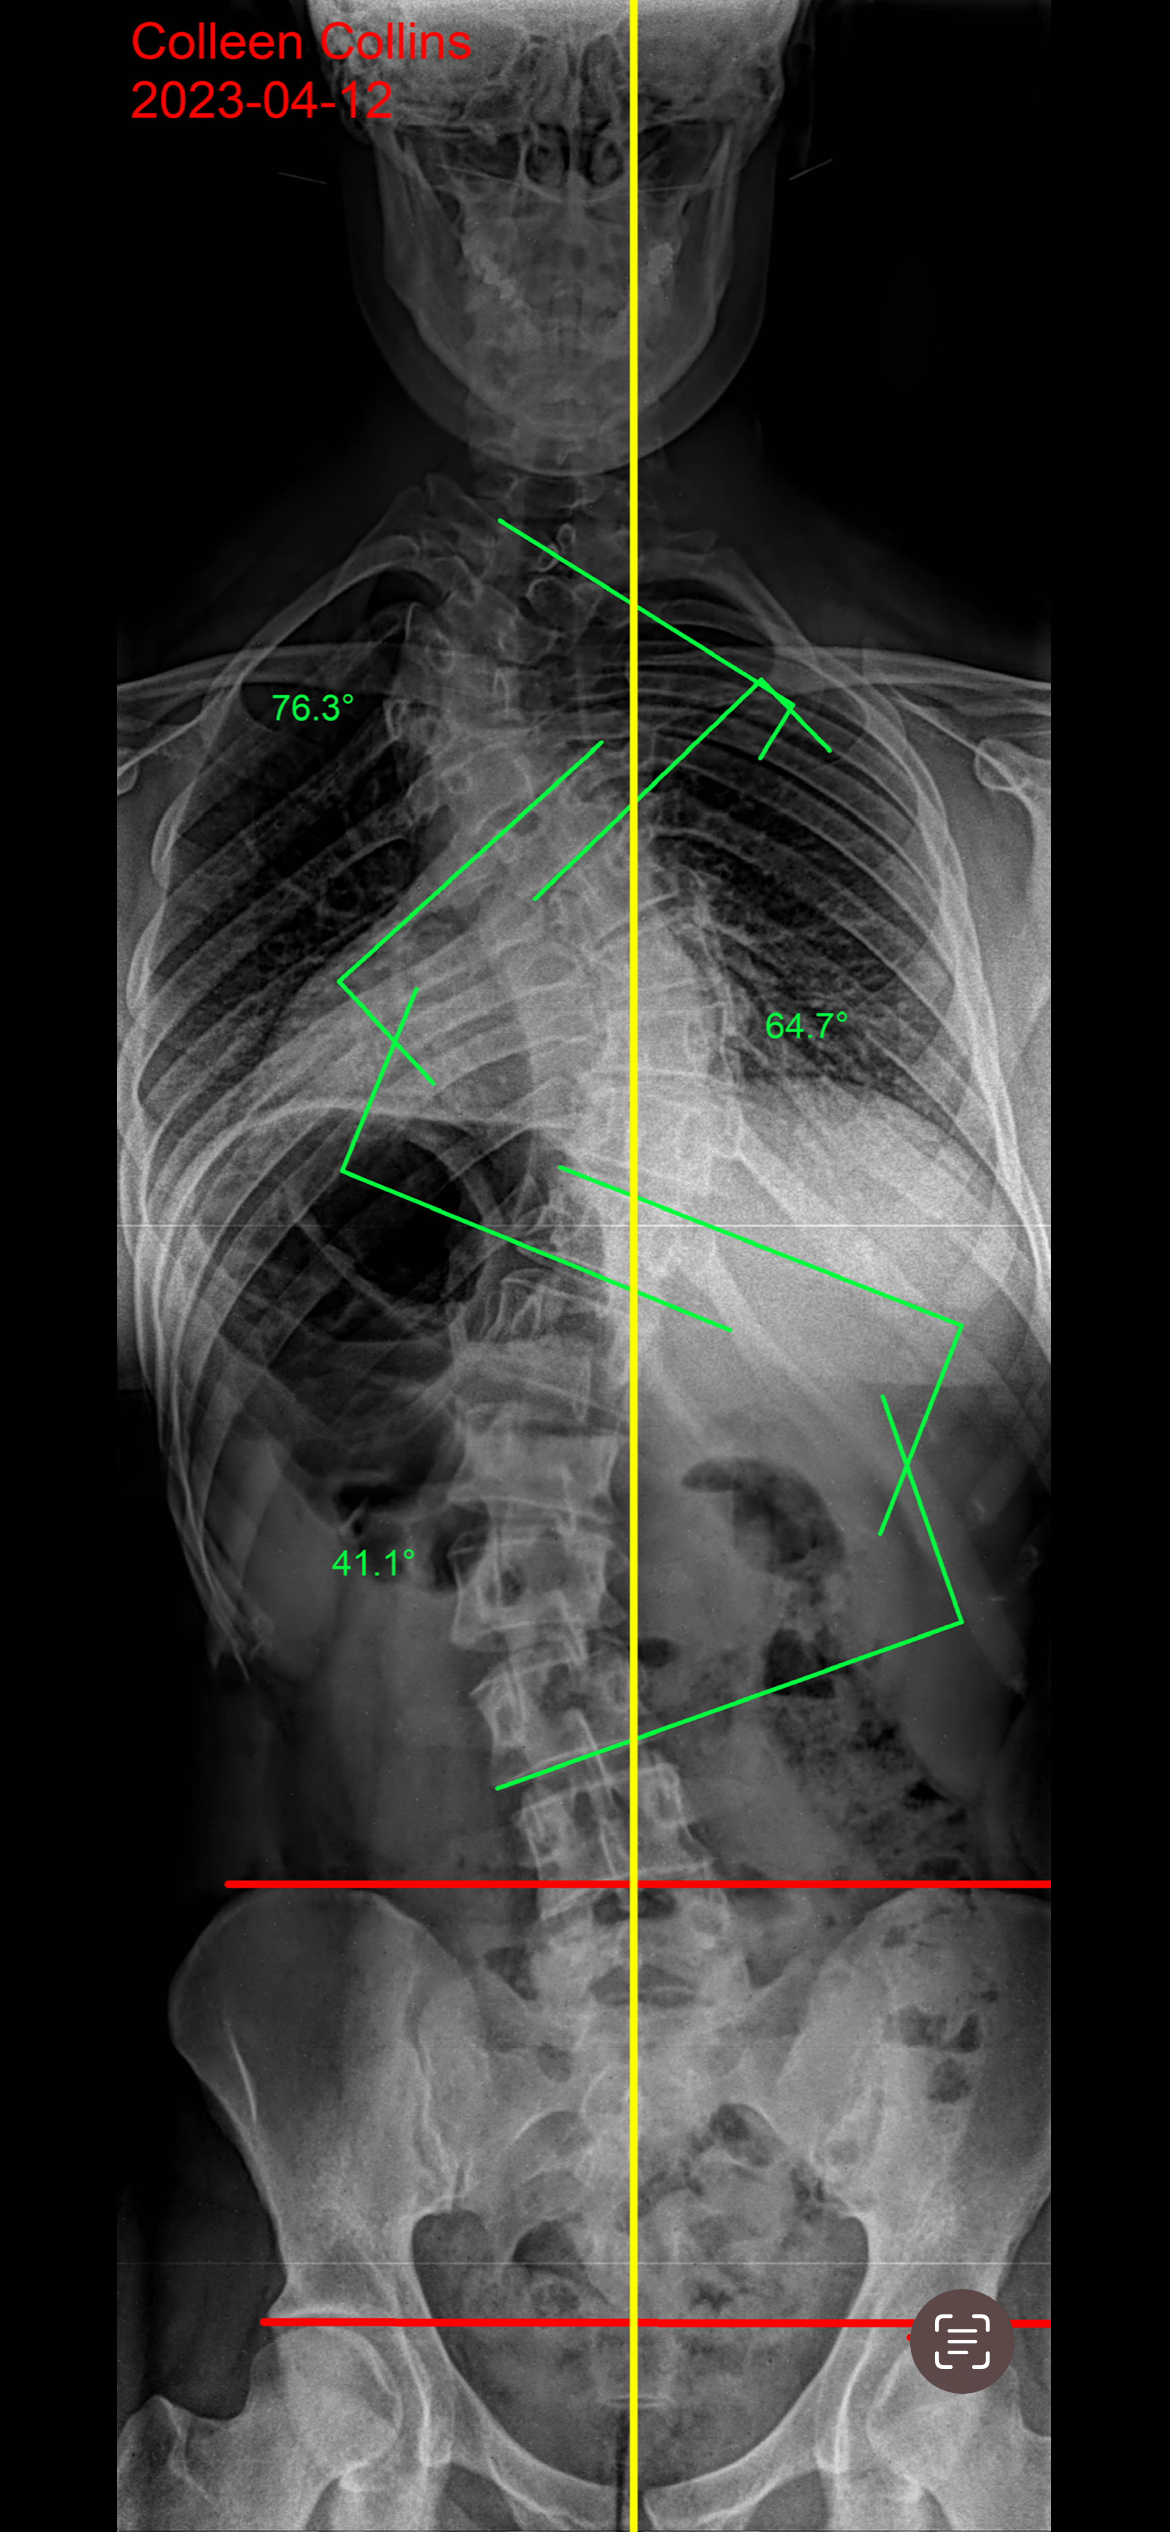

Scoliosis is a condition where the spine curves sideways, often in a C or S shape, and is most commonly found in adolescents. The cause is usually unknown, but it can also result from congenital spine issues or neuromuscular conditions like cerebral palsy.

Scoliosis is diagnosed through a physical examination and confirmed with imaging tests, such as X-rays, which help determine the degree of the spinal curvature.